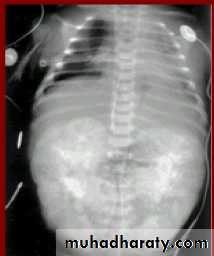

Horse shoe kidney -Kidneys may fail to separate.

-Almost invariably the lower poles remain fused.

-The kidneys axes are more parallel to the spine and malrotated.

-Diagnosis can be made by plain x-ray in some cases.

IVU shows

1. The kidneys at low position .

2.Close to the spine with long axis parallel to the spine .

3. Malrotation manifested by medially directed calyces.

4- The renal pelvis and ureters are anterior and lateral in position .